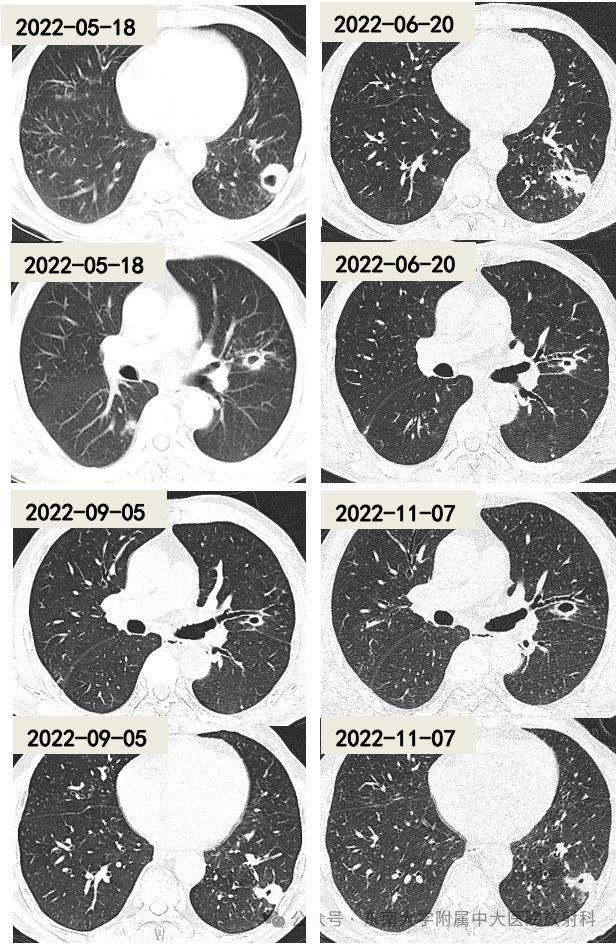

• 男 ,69岁

• 主诉:因“体检发现肺结节 4 天”入院

• 患者4天前于外院体检发现肺结节。外院胸部CT提示:①左上肺、左下肺结节伴空洞形成,周围见多发小结节,性质待定,结核待排;②纵隔内见数枚淋巴结,短径约5–8mm。近1个月来,患者偶有咳嗽、咳黄白色痰。为求进一步诊治,至我院门诊就诊,以“肺占位性病变”收治入院

• 辅助检查:白细胞计数 5.53×10⁹/L,中性粒细胞计数 3.88×10⁹/L,淋巴细胞计数 1.23×10⁹/L,超敏C反应蛋白 3.56 mg/L(↑)

• 影像检查:2022-05-18、2022-06-20、2022-09-05、2022-11-07;门诊号:0003095519

影像学表现